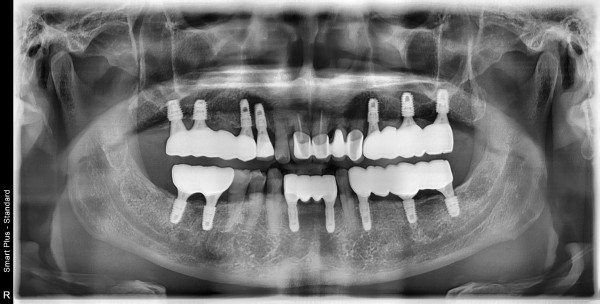

56세 이**님의 치료후

치료종결일 2021.06.08

촬영장소 온가주치과의원